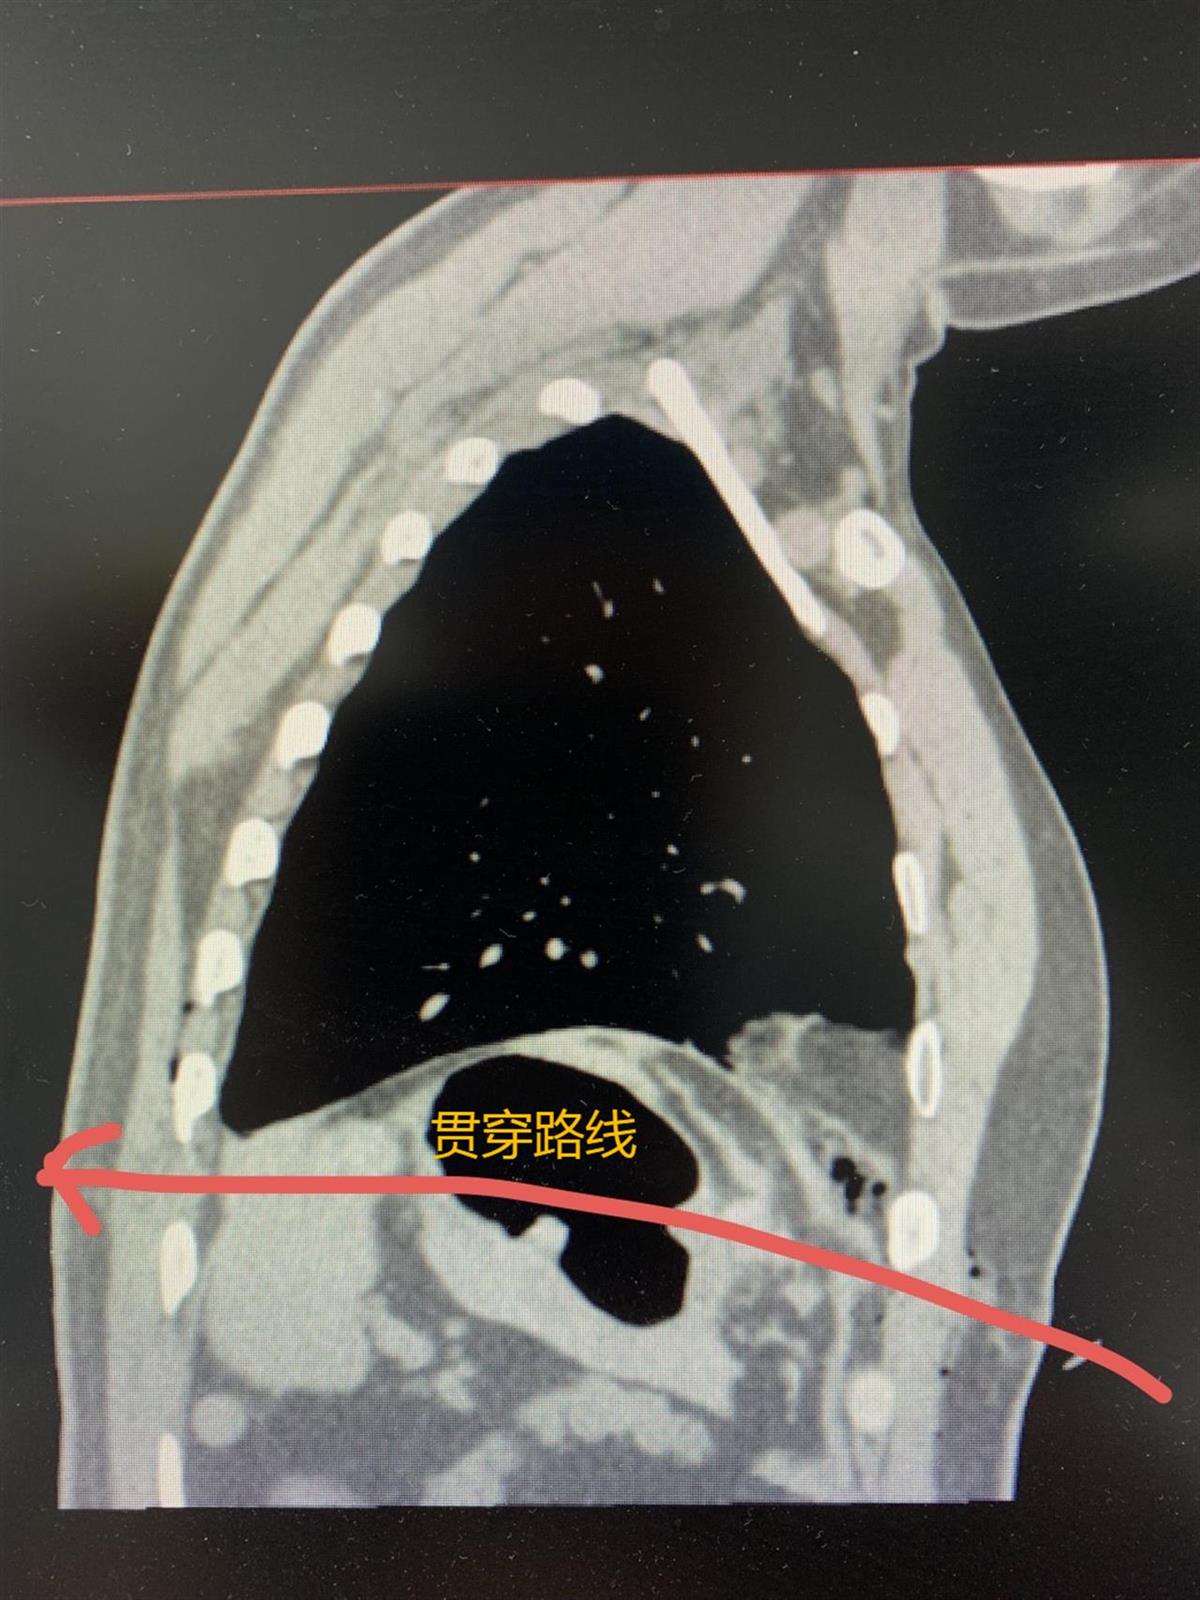

宋师傅是名装修工,一次工作中,他操作钉枪没注意,不慎被钉枪射中左腹,钉子贯穿身体致胃、脾、肺受损。同事赶紧将他送到武汉科技大学附属天佑医院急诊科就医。该院急诊科李勇医生接诊后,发现宋师傅左胸腹交接处有灼烧样拇指大小的红色血洞,钉子贯穿患者身体后挂在了其外套上。由于钉子射入的位置在胸腹部交界处,李医生担心伤及到重要脏器及大血管,立即安排做胸腹急诊CT,同时联系普通外科、心胸外科紧急会诊。

钉子贯穿患者身体(通讯员供图)

检查结果发现患者胃贯穿,脾脏、左肺下叶受损,情况十分紧急,医疗团队以急诊绿色通道将患者送入手术室。同时,医护人员紧急联系家属,在取得家属同意后进行手术。

该院普外科主任王益、吴刚与心胸外科主任高威以及刘赋斌、李笑东医生联合上台手术。手术探查发现,患者腹腔积血约100毫升。吸净积血后发现,胃穿透性损伤、脾上极贯通伤,局部有活动性出血。医疗团队吸净积血及消化液等液体后,进一步行胃穿孔修补、膈肌修补术。对于脾损伤一般施行脾切除术,考虑到患者是体力劳动者,又是家里顶梁柱,术中与家属充分沟通后,决定实行保脾手术。手术历经7个小时,取得成功。